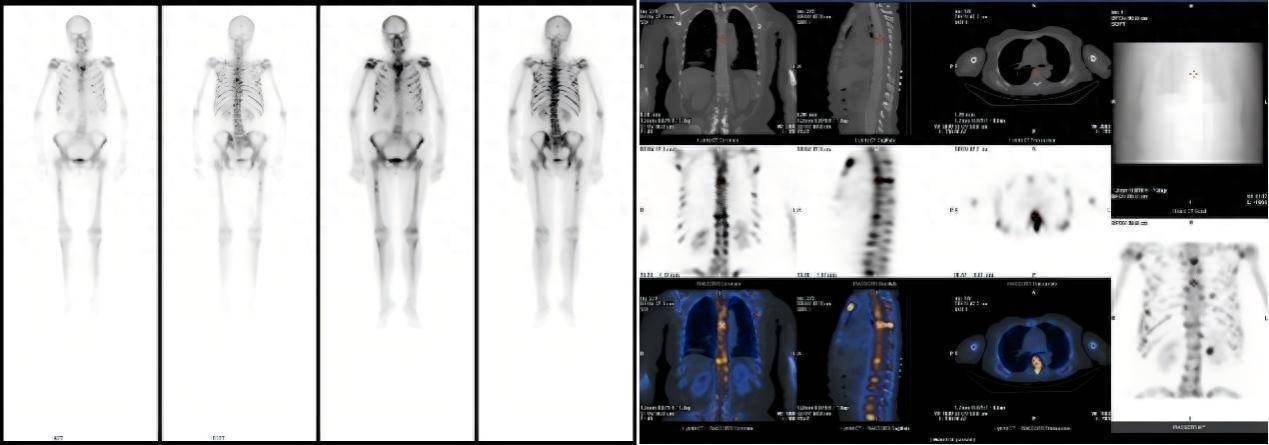

患者因不明原因发热、剧烈骨痛伴体重骤降前来就诊。入院后,全腹及胸部CT未见明显异常,但血常规提示白细胞、淋巴细胞、血小板及红细胞计数均显著降低。为进一步探明病因,临床医生安排了全身骨扫描(SPECT/CT),结果显示全身多处骨骼放射性浓聚,初步怀疑为肿瘤骨转移,其诊疗方向指向实体肿瘤,但其CT却未见明显病灶,诊断陷入了困境。临床医生随即安排可以全身扫描尤其对肿瘤病变尤为敏感的PET-CT检查。

△患者全身骨扫描(SPECT/CT)核医学显像图